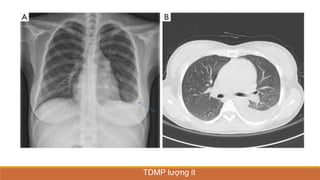

TDMP lượng ít

TDMP lượng vừa

TDMP lượng nhiều

TDMP ÁP LỰC, ĐẨY TRUNG THẤT VỀ PHÍA ĐỐIDIỆN